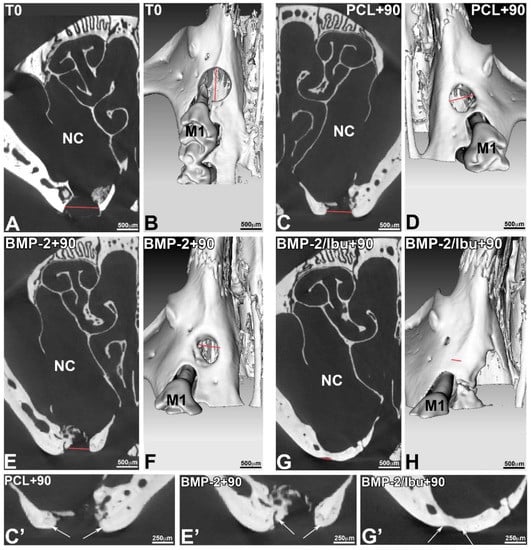

3.4. Maxillary Bone Regeneration Based on Nanoreservoirs Functionalized PCL with BMP-2 and BMP-2/Ibu